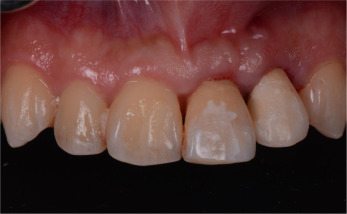

A twenty-six year old male patient was referred for the management of the symptomatic maxillary left central and lateral incisors. The incisors were diagnosed with external root resorption due to history of trauma. The long-term endodontic prognoses were assessed to be poor (Figs. 1 a, b and 2 ).

Fig. 1.

(a) Labial view of the pre-operative clinical condition. (b) Palatal view of the pre-operative clinical condition.